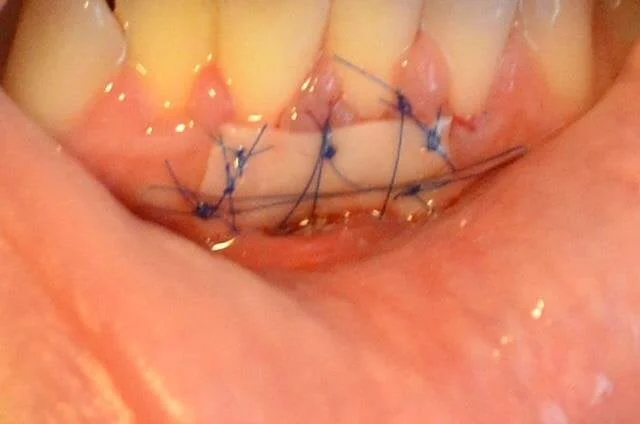

8. Операция по пересадке десны